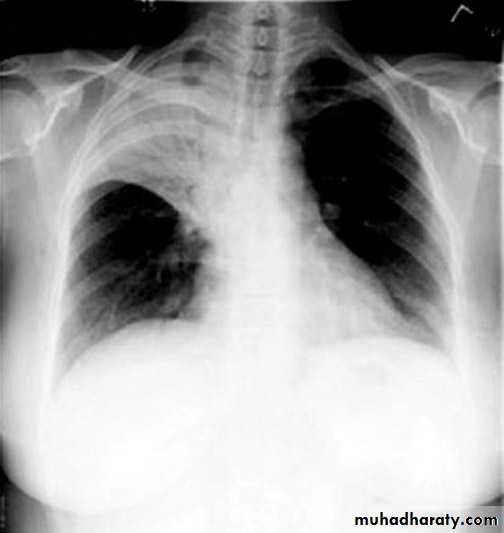

48.opasified hemi thorax Total collapse

Homogenus opacity of the right hemithorax with shifting of the trachea to the same side48.opasified hemi thorax Total consolidation

Homogenus opacity of the left hemithorax with central trachea

Total collapse

Homogenus opacity of the left hemithorax with shifting of the trachea to the same sidePleural effusion